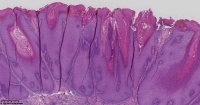

脂溢性角化症?

性别

女

年龄

61岁

一般病史

背部皮肤包块

标本名称

图4

脂溢性角化病